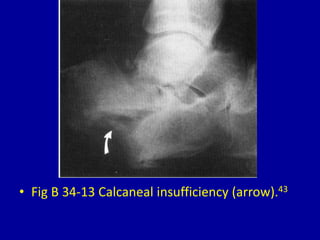

This document provides descriptions and images of avulsion injuries at various anatomical locations in the body. Avulsion injuries refer to the tearing away of a tendon, ligament, or muscle from the bone. The document lists 17 figures showing examples of avulsion injuries at locations such as the ischial tuberosity, anterior superior iliac spine, anterior inferior iliac spine, symphysis pubis, lesser trochanter, greater trochanter, fibular head, tibial eminence, posterior cruciate ligament, tibial tuberosity, inferior pole of the patella, calcaneal tuberosity, anterior and posterior capsule of the ankle joint, greater and lesser tuberosity of the